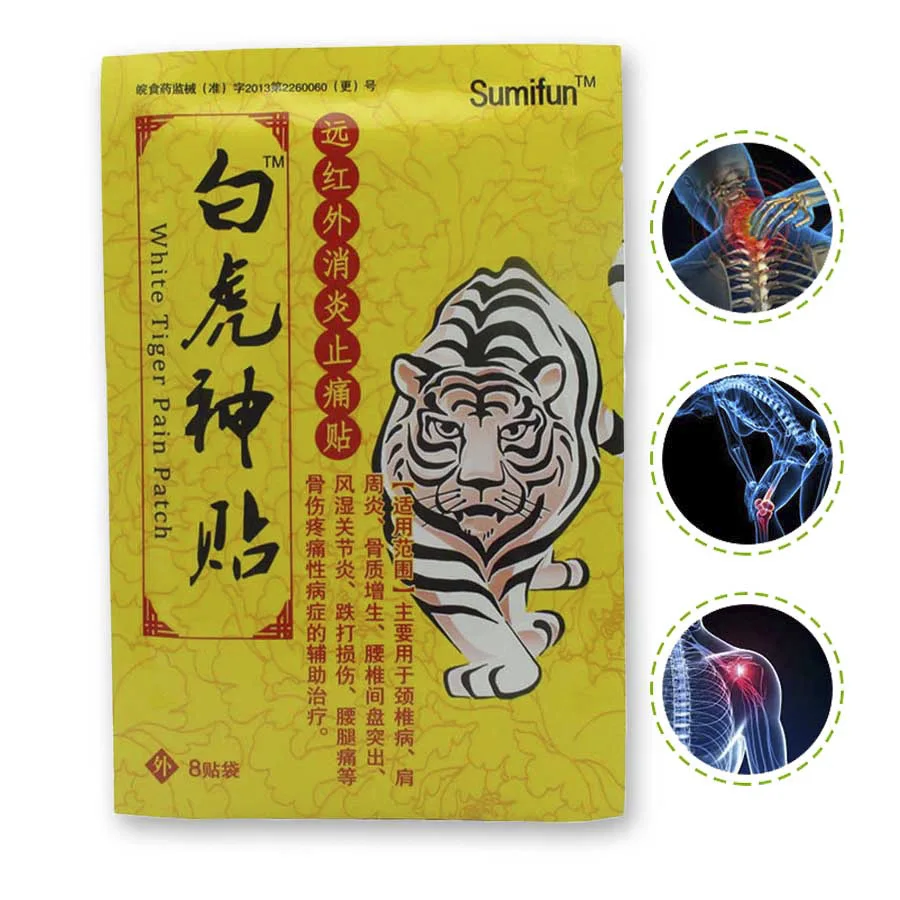

Пластырь от боли CN Herb White Tiger, противовоспалительная анальгетическая паста с дальним инфракрасным излучением, 8 паст